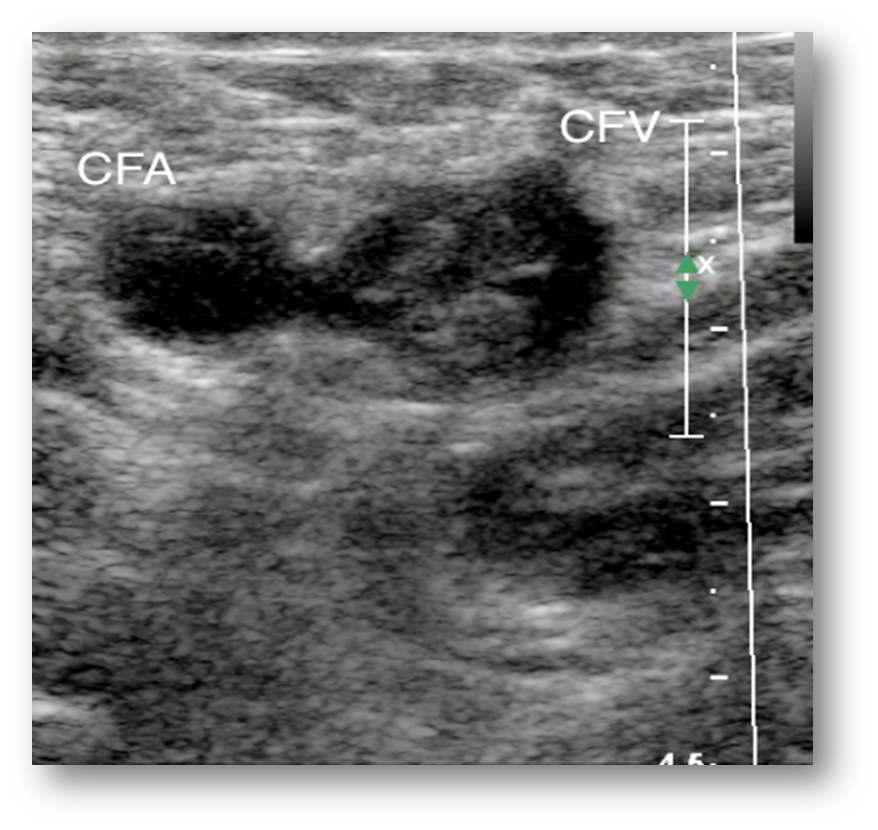

What is this image showing?

acute blood clot